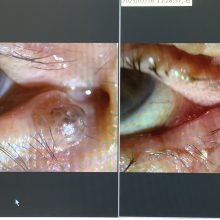

今日の外来では、先週、涙管閉塞による流涙症で涙管チューブの挿入を行った方の経過観察の診察がありました。

この方は、昨年の春に、シニアクラブで僕が話した加齢にまつわる眼の話を聞いてくださり、こちらに来てくださり、昨年の12月に右下まぶたの外反症の手術を受けていただき、その後、以前からあった右眼の涙がずっと出てしまう症状をなんとかしたいということで今回の手術になりました。年齢が91歳と90歳を超えても症状をよくしたいという気持ちも立派だと思いますし、実はお住まいも茨城県なのにわざわざ神奈川の当院まで来てくださる気力と体力が素晴らしいなと思いました。症状もよくなったということでよかったです。